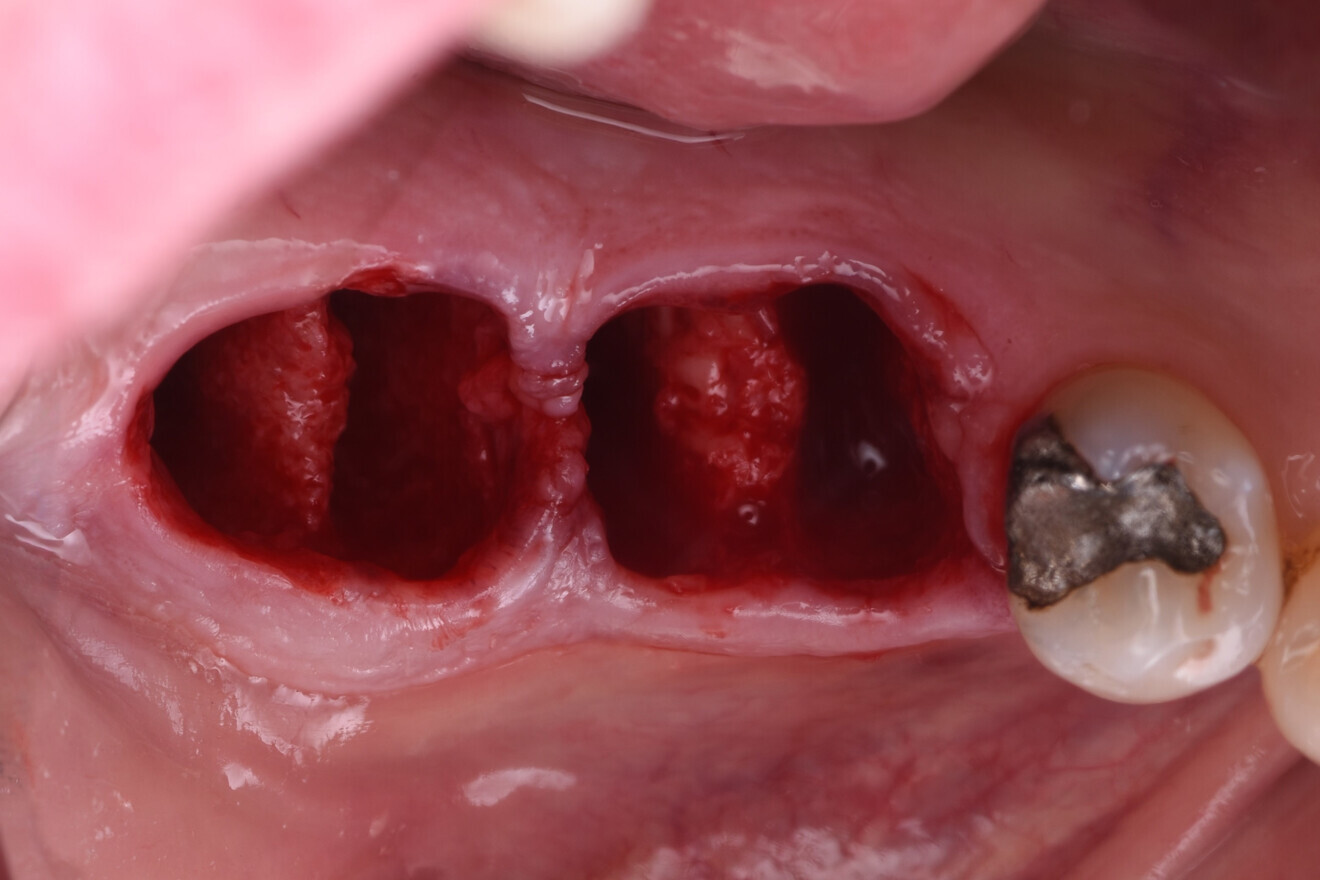

Fig. 7: Existing roots sectioned to allow atraumatic extraction.

The failing teeth were sectioned and extracted atraumatically to preserve the surrounding bone (Fig. 7). The sockets were thoroughly debrided using Lucas curettes to remove any residual infection or granulation tissue (Fig. 8).